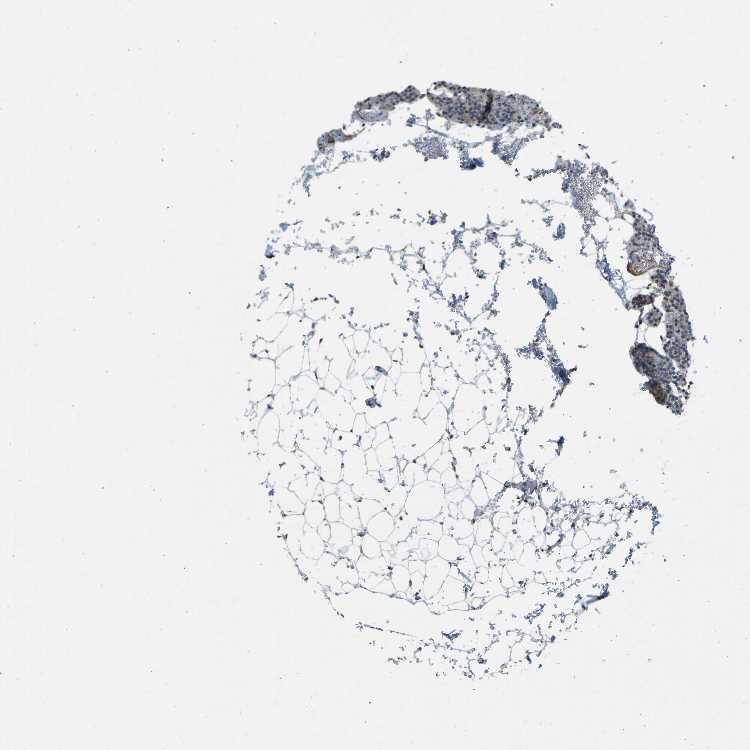

TISSUE PRIMARY DATA PARATHYROID GLAND Show tissue menu

Parathyroid gland

PARATHYROID GLAND - Expression summary

PARATHYROID GLAND - Antibody stainingi

Antibody staining in the annotated cell types in the current human tissue is reported as not detected, low, medium, or high, based on conventional immunohistochemistry profiling in selected tissues. This score is based on the combination of the staining intensity and fraction of stained cells.

Each image is clickable and will lead to virtual microscopy that enables deeper exploration of all samples and also displays staining intensity scores, fraction scores and subcellular localization as well as patient and tissue information for each sample.

Antibody HPA001934Antibody CAB018622

Glandular cells Not detectedLow